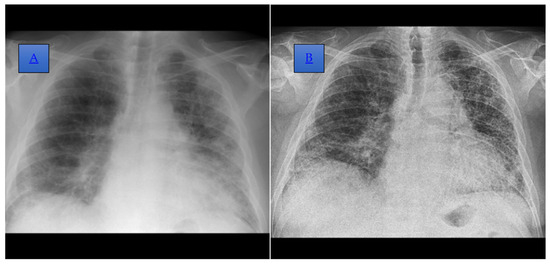

Figure 2. (A) Posteroanterior incidence chest radiograph, performed in 2021, which highlights the accentuation of the bilateral juxtahilar and basal, interstitial, and peribronchovascular pattern, which is more obvious on the left side. A reduction in lung transparency bilaterally, more obviously the left subpleural, is also shown. (B) Posteroanterior incidence chest radiograph, performed in 2022, where an accentuation of the perilobular interstitium with a reticular and pseudo-honeycomb appearance and on the basal right thickening of the pleuritic septa, dispersed in the left 2/3 lobe and the external basal in the right lobe, is shown.